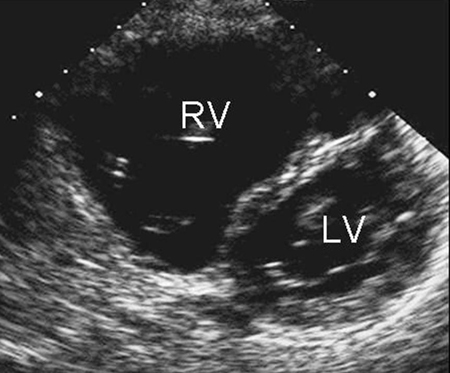

CXR is not helpful in determining the subtype and may be normal with a small ASD. ECG may also be normal in small secundum, sinus venous, and unroofed coronary sinus ASDs. With a larger shunt, there may be right atrial enlargement, right ventricular hypertrophy, or right axis deviation.[Figure caption and citation for the preceding image starts]: Parasternal short axis echocardiographic image demonstrating right ventricular enlargement in a patient with an ASD. (RV) right ventricle; (LV) left ventricleImage courtesy of Patrick W. O'Leary, MD [Citation ends].